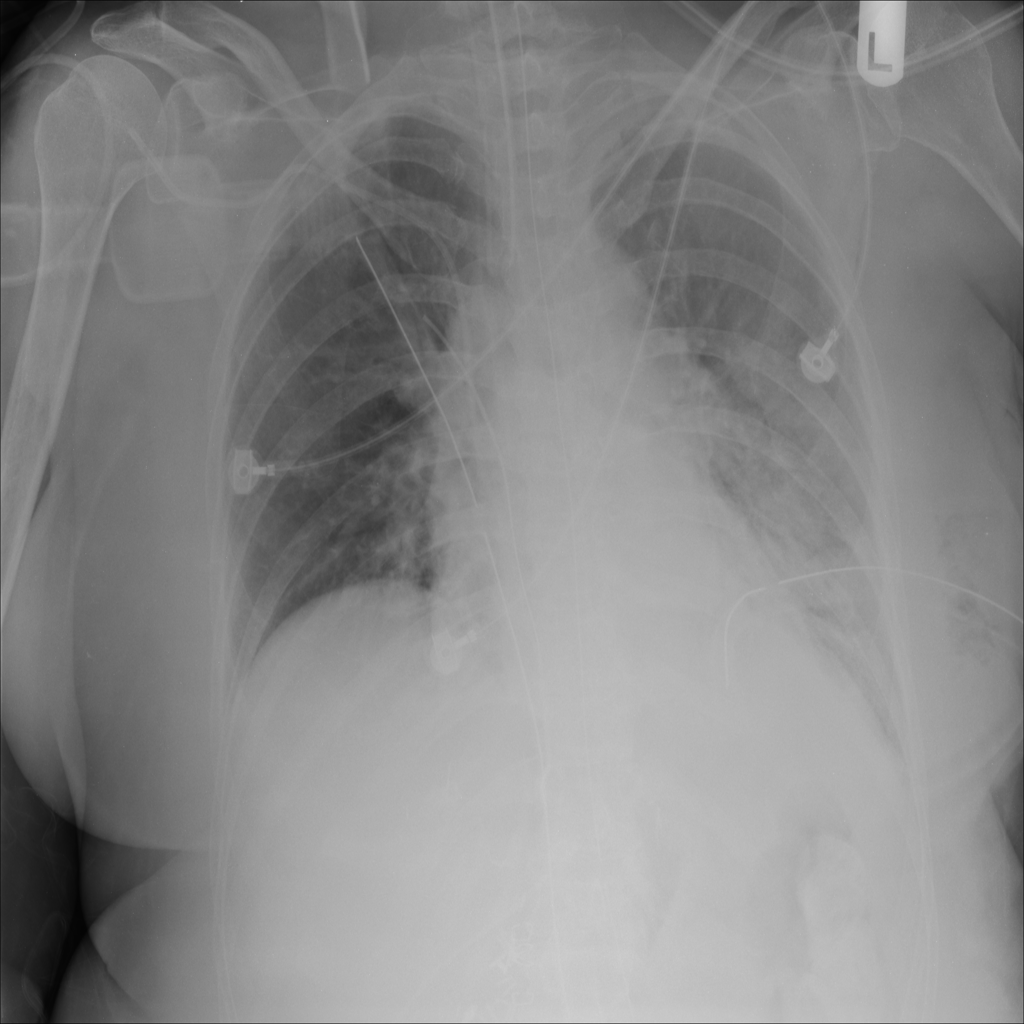

PAT-B0DB · IMG-003Emphysema

PAT-B0DB · IMG-003

PA